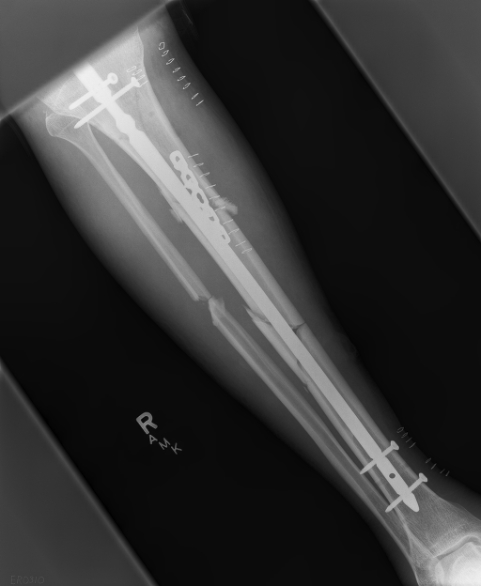

These can be challenging. I agree w/ all Dr. Carr's points. My preference to prevent the deformity is to use an anteromedial plate. See attached case.

![]() |